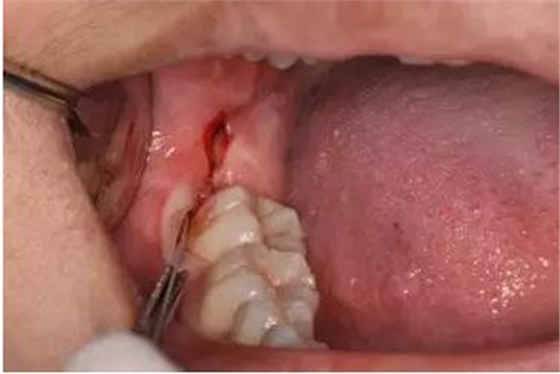

圖11.以頰側(cè)骨板做支點(diǎn)、往上脫位

圖12. 近中、頰側(cè)兩個(gè)部位用挺使48牙冠完全脫位

圖13.清理牙槽窩、對(duì)位傷口

圖14.僅在遠(yuǎn)中縫合兩針,不宜太緊。